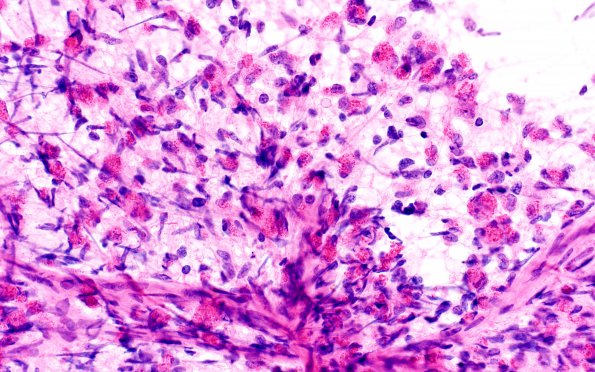

Washington University Experience | NEOPLASMS (GLIAL) | Glioblastoma, granular cell type | 3A1 Glioblastoma, granular cell type (Case 3) Sm 40X 1

Case 3 ---- The patient is a 54 year old man who presents with 5-6 day history of bifrontal sharp headaches increasing in severity when coughing and more frequently occurring in the morning. MR scan shows a large right cerebral enhancing mass suggestive of glial neoplasm. Clinical diagnosis: Cranial mass. Operative procedure: Biopsy. ---- 3A1,2 An intraoperative smear preparation shows numerous granular tumor cells. On such a preparation they may be mistaken for eosinophilic granular bodies (usually EGBs don’t have nuclei) or even macrophages in a questionable demyelinative process (H&E).